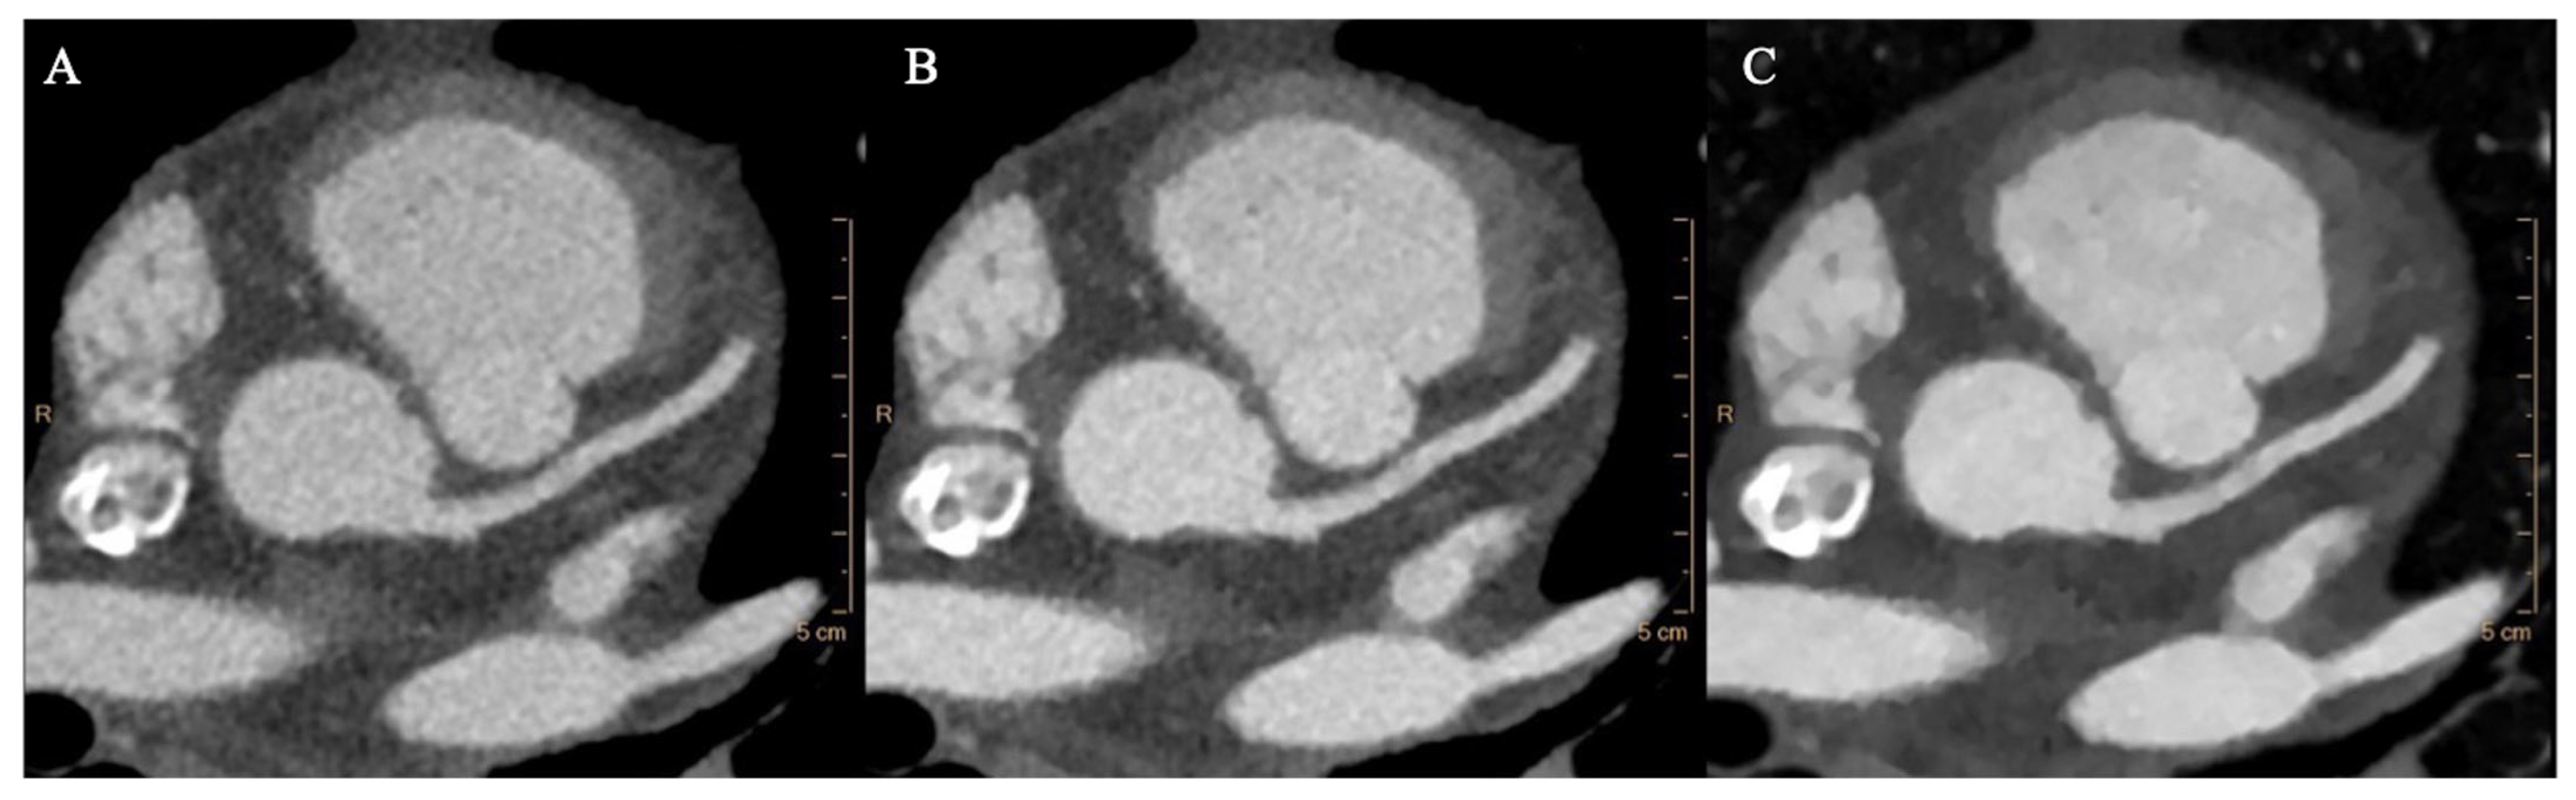

3.2. Objective Image Quality Analysis

3.3. Subjective Image Assessment